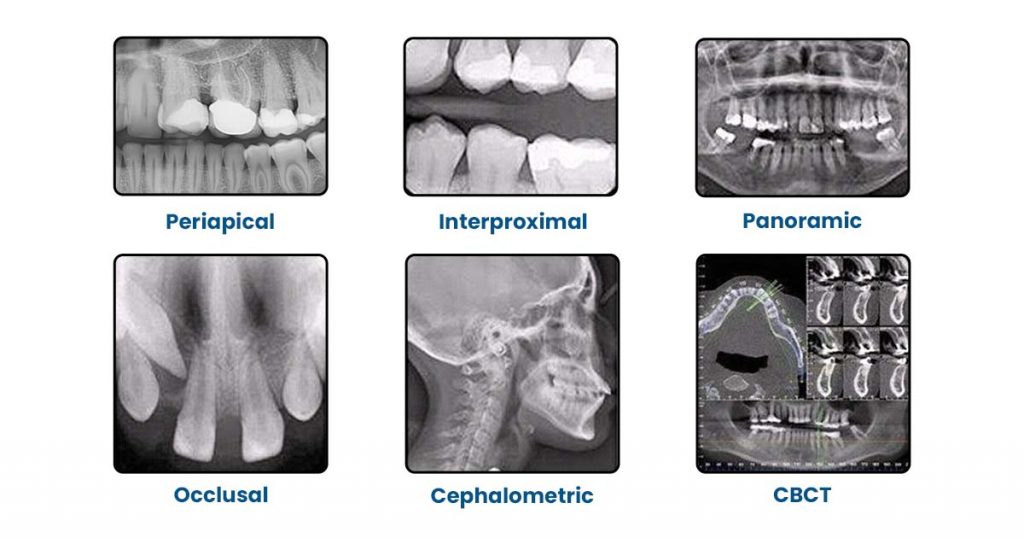

Types of Dental X-Rays You Must Know

How to read dental x-rays? Before answering this question, you must understand the types of dental x-rays.

a) Periapical X-Rays

Used for:

- Assessing Root Structure

- Periapical pathology (abscess, cyst, granuloma)

- Root canal anatomy and Working Length estimation

b) Bitewing X-Rays (BWX)

- Interproximal Caries Detection

- Bone level evaluations.

- Existing Restoration placement.

c) Panoramic X-Rays (OPG/PAN)

- Orthodontics evaluation before starting the treatment.

- Impacted third molar.

- Fractures of the jaw

- TMJ evaluation

- Developmental anomalies

d) Occlusal X-Ray

- Captures a wide view of the maxilla or mandible to detect large lesions, fractures, or impacted teeth.

- Shows buccal–lingual tooth position.

- Helpful for locating foreign bodies or supernumerary teeth.

- Useful for trauma cases, identifying jaw fractures and anterior pathologies.

- Useful for children or those with gag reflex issues.

e) Cone Beam Computed Tomography (CBCT)

- Implant planning.

- Evaluation of bone, nerves, and roots in 3D.

- Useful in identifying complex pathology.

f) Cephalometric

- Gives a side-view of the skull and jaws.

- Helps assess jaw growth and alignment.

- Measures Skeletal and Dental Relationships.

- Used to track Orthodontic treatment progress.